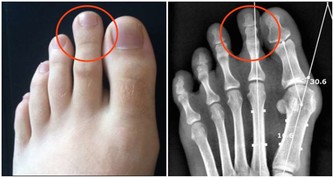

當人們長期性的走路久時,下肢靜脈壓力相應的較低,下肢靜脈,淋巴液回流受阻,從而引起膝蓋酸腫,因而走路久了需要休息。如果長期性走路久了引起膝蓋酸痛,就需要到正規的醫院對膝蓋部位做x光片檢查骨質情況,再聽醫生的話進行治療。

值得注意的是,膝蓋痛有可能是缺鈣、涼風寒濕痺證、骨質增生、受涼受風受濕、肝腎虛弱等所引起的。隨著年齡的增長,站立或者走路久了,膝關節都可能會發生退性行病變。初期,起病緩慢者膝關節疼痛不嚴重,可持續性隱痛,氣溫降低時疼痛加重,與氣候變化有關。

晨起後開始活動,長時間行走,劇烈運動或久坐起立開始走時膝關節疼痛僵硬,稍活動後好轉,上、下樓困難,下樓時膝關節發軟,易摔倒。蹲起時疼痛,僵硬,嚴重時,關節酸痛脹痛,跛行,關節功能受限,以下蹲最為明顯,伸屈活動有彈響聲,部分患者可見關節積液,局部有明顯腫脹、壓痛現象,合併風濕病者關節紅腫、畸形。